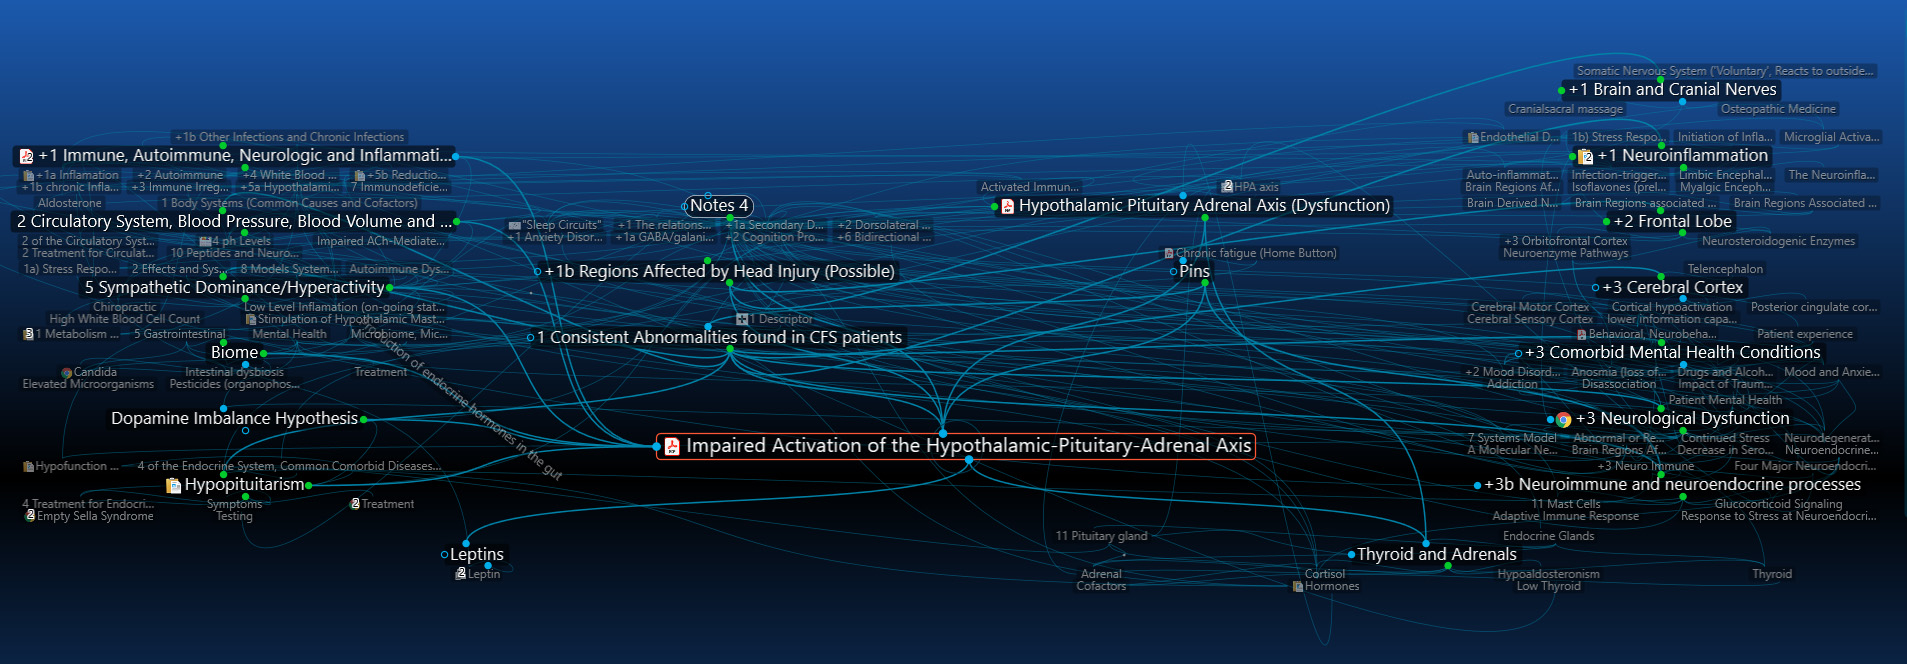

8) Hypothalamus